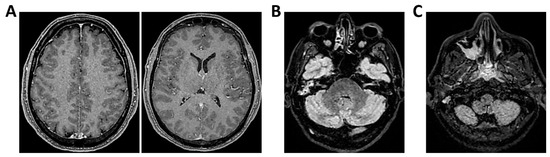

Background: Meningoencephalitis is a complex inflammatory condition of the CNS that can result in significant morbidity and mortality in critically ill adults. Accurate and timely neuromonitoring is essential for guiding management and improving outcomes. This study aimed to descriptively evaluate the prognostic value of early TCCD monitoring, particularly the pulsatility index, and its integration with conventional and perfusion MRI in patients with meningoencephalitis. Methods: We present an observational, retrospective, cohort study involving ten adult patients (median age 56 years, IQR 45.5–68.5; mean 55.9, range 35–76) with neurological syndromes caused by suspected or confirmed infectious meningoencephalitis. Etiologies included bacterial meningitis/meningoencephalitis (50%), viral meningoencephalitis (10%), neurotoxoplasmosis (10%), progressive multifocal leukoencephalopathy (10%), and undetermined origin (20%). Patients underwent TCCD and MRI within 24 h. In five cases, standard MRI sequences were acquired, while in the remaining five, perfusion imaging was performed using Arterial Spin Labelling (ASL). A favorable outcome was defined as survival with neurological recovery (Glasgow Outcome Scale > 5) at ICU discharge. Results: TCCD-derived PI provided valuable information on cerebral hemodynamics. PI values ≤ 1.25 were associated with favorable clinical outcomes and symmetrical MRI findings. Conversely, PI > 1.25 correlated with poor prognosis and often preceded MRI-detectable structural damage. When combined with ASL, PI mirrored the detected perfusion asymmetries and was associated with poor prognosis in fatal cases. Conclusions: Bedside TCCD can offer real-time assessment of cerebrovascular dynamics and, when integrated with conventional and ASL MRI, could enhance the understanding of pathophysiological processes in meningoencephalitis, supporting timely and informed decisions in neurocritical care.